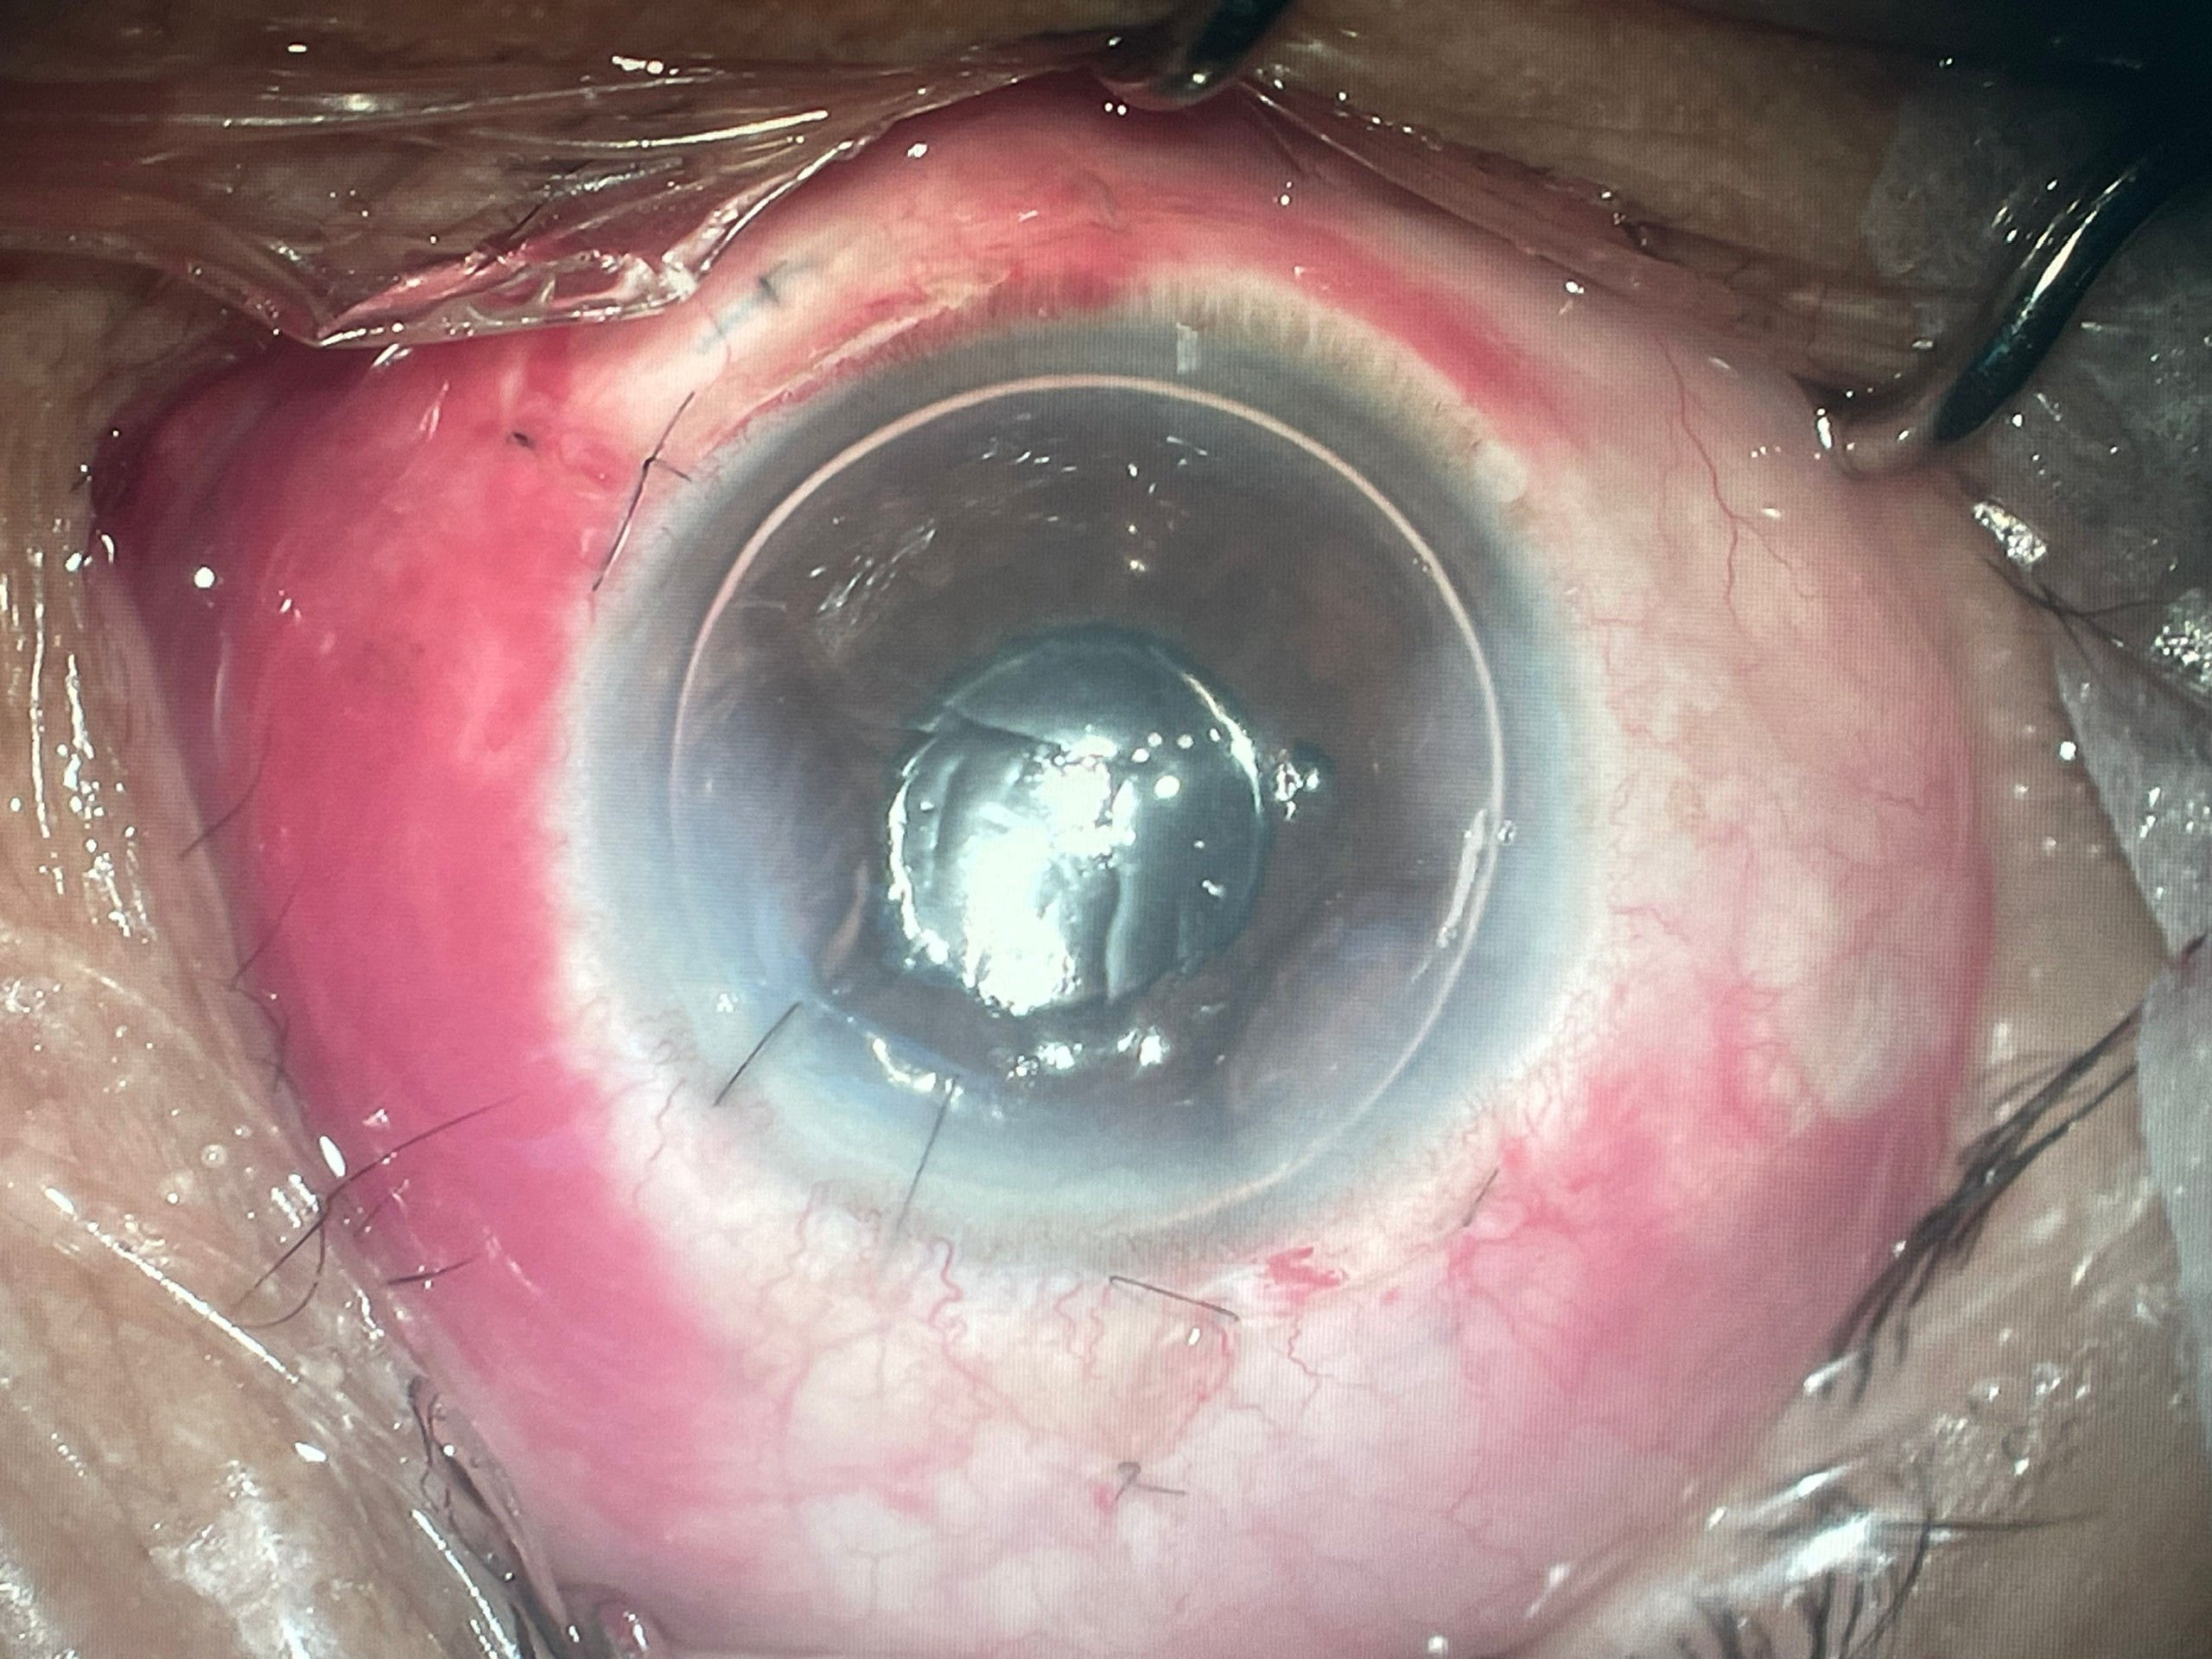

+ Phẫu thuật lấy thủy tinh thể bị lệch và cố định thủy tinh thể nhân tạo

| TTT bị lệch (không hoàn toàn) | Phẫu thuật cố định IOL | Sau phẫu thuật |